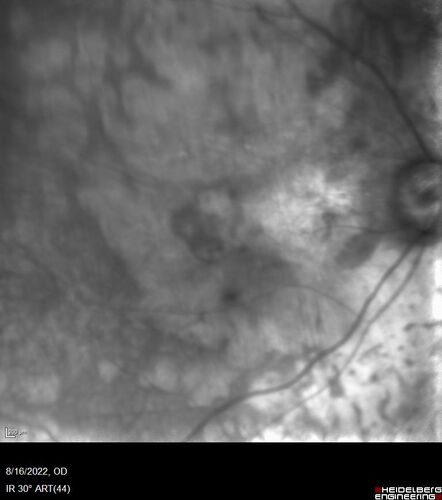

Optic Disc Melanocytoma - Atypical

45 year old female with normal vision and optic nerve lesion in the left eye. VA 20/16 OU. Extensive testing was normal including brain and orbit MRI. The lesion has been stable for 5 years.

AMD End stage both eyes - scar OD - GA OS